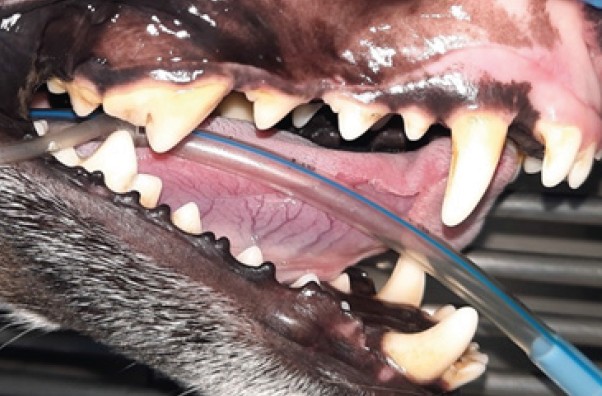

Fig. 4. Dental calculus stage 1 (109, 108, 104)

Source: VTC "Dentalvet".

Fig. 5. Intraoral radiograph for stage 1 dental calculus